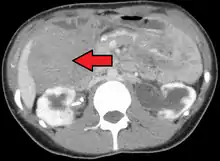

| Desmoid tumor as seen on CT scan | |

MRI or CT imaging scans are commonly used for monitoring.[45][1]